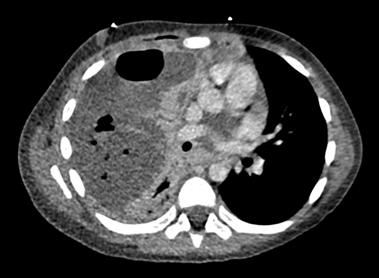

The following day, the infant presented with new lesions and nodular scabies was suspected. The delta-wing jet sign observed on direct dermoscopy confirmed the diagnosis (Figure 2). The patient and his parents were treated with topical 6% sulfur ointment for three consecutive days, repeated after seven days.

Figure 2. Dermoscopy of the lesions: delta-wing jet sign, a triangular structure at the end of the central S-shaped burrow.